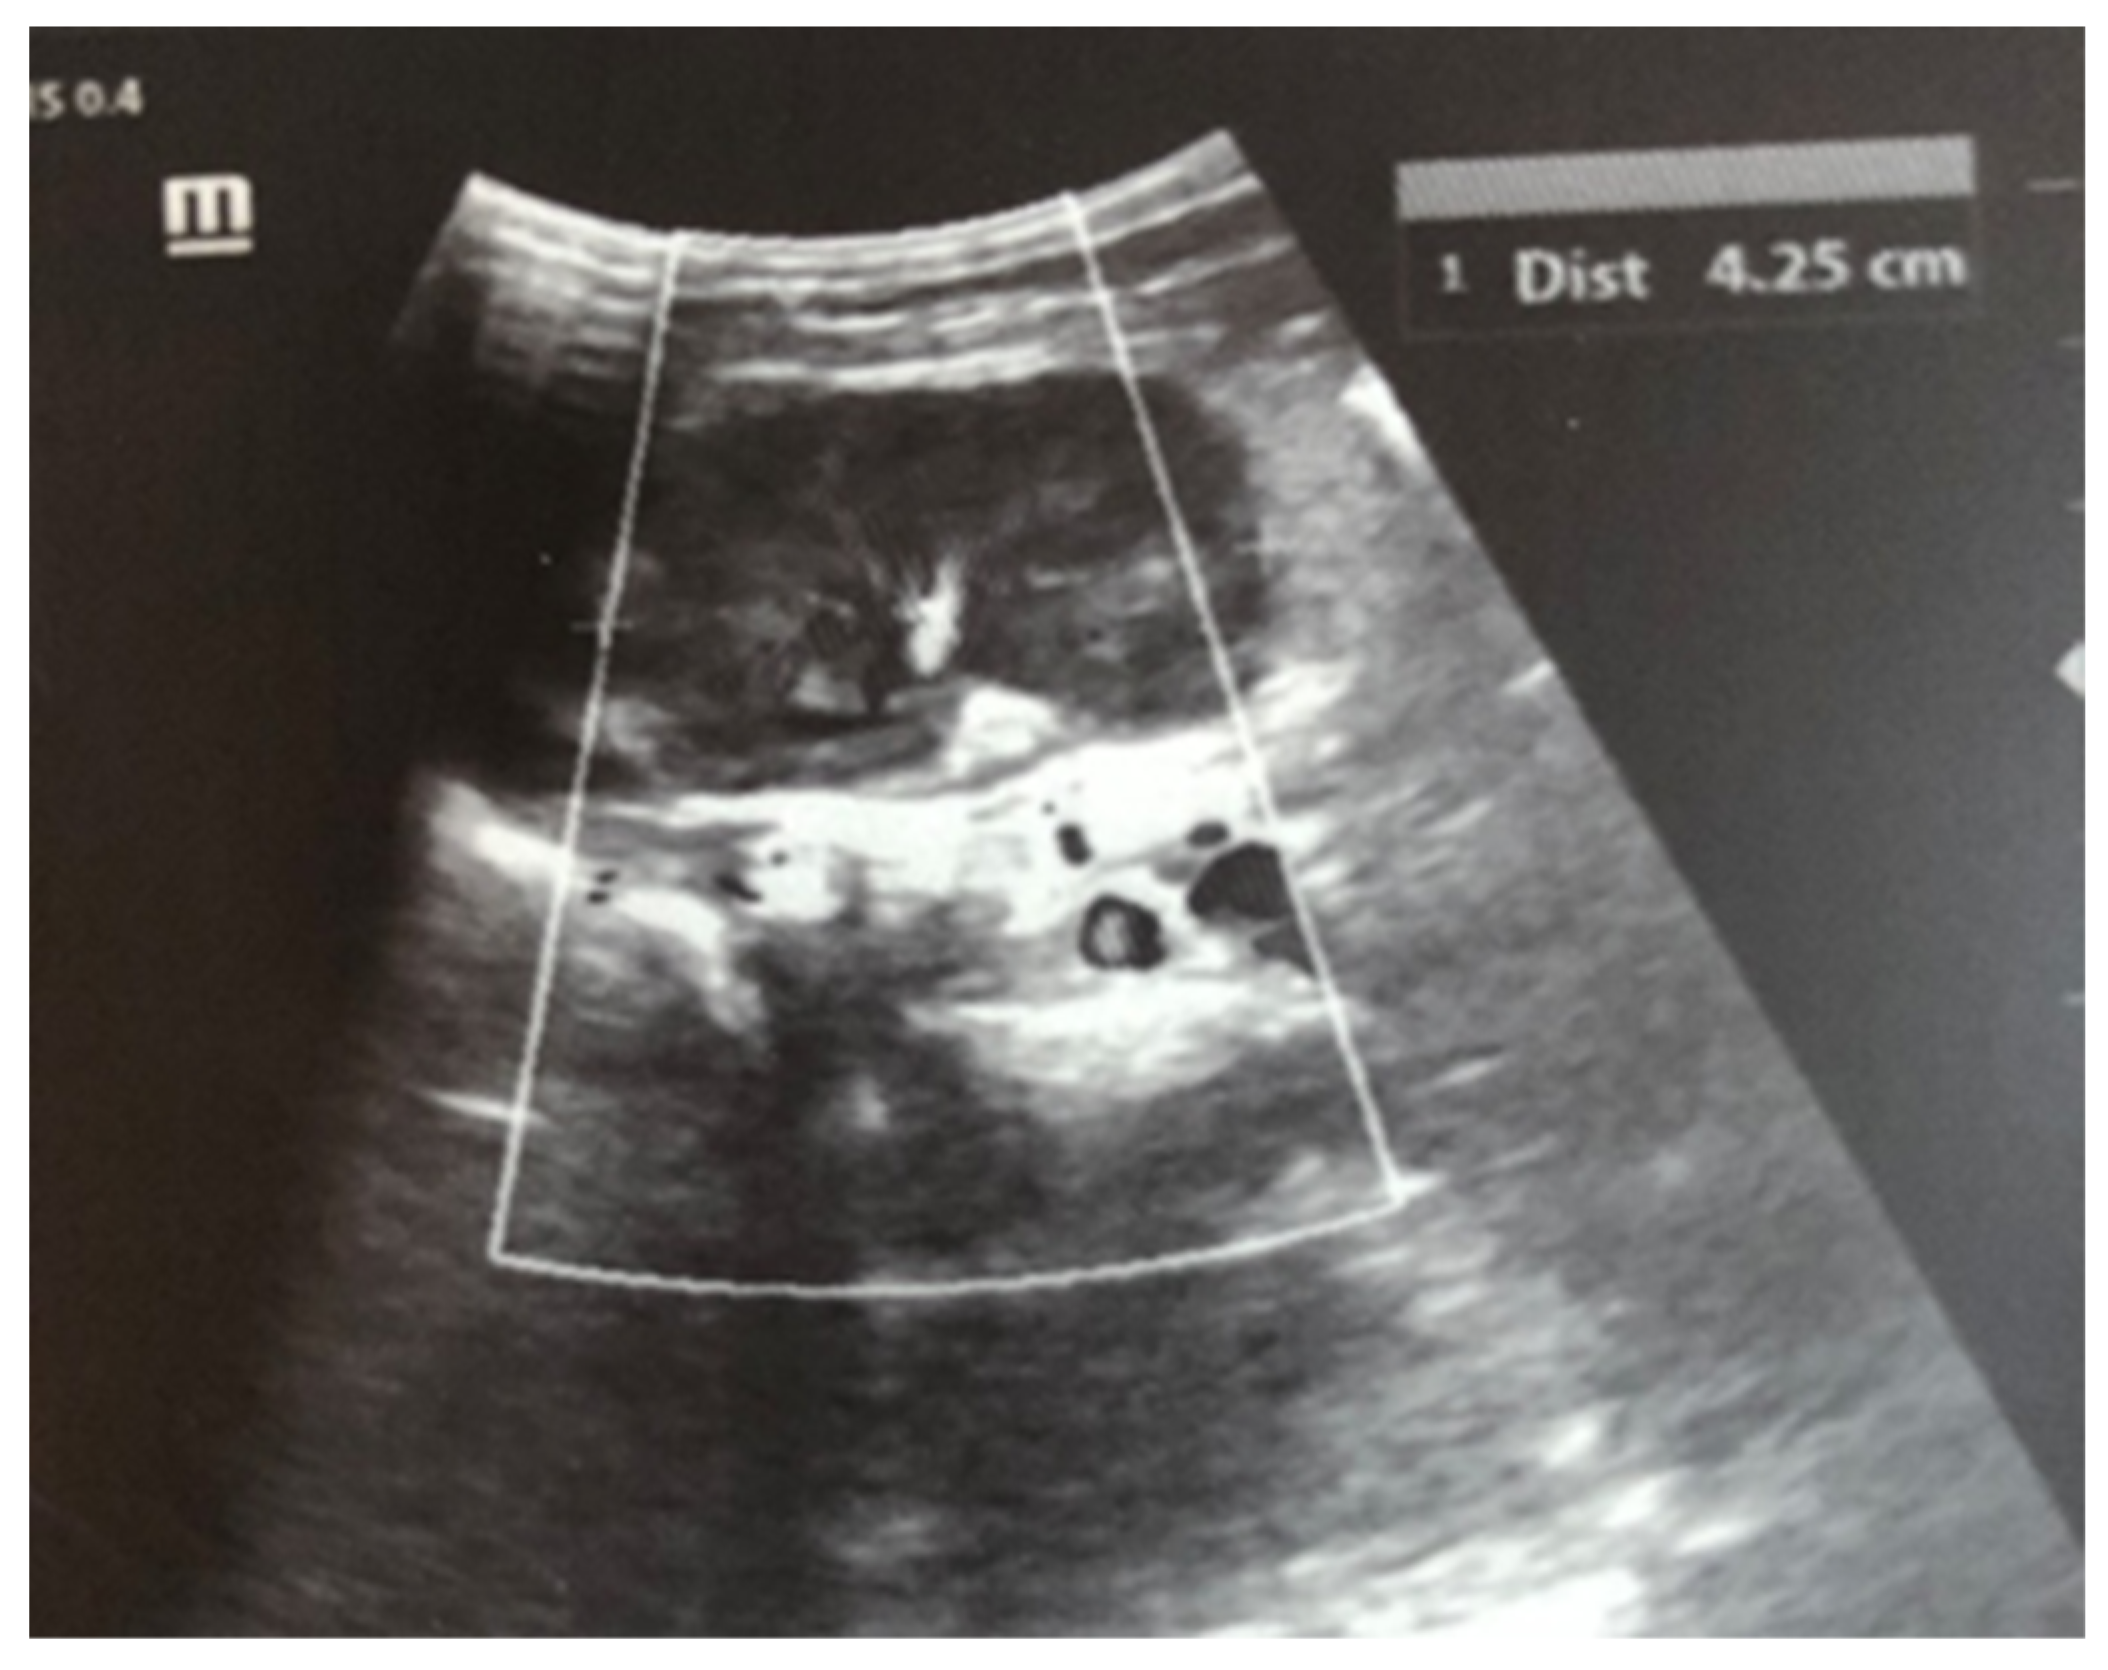

After admission to the NICU, the neonate was found febrile, with symptoms of multiple organ failure: respiratory system failure requiring treatment with Curosurf and mechanical ventilation; renal failure with symptoms of oliguria, macroscopic hematuria, and an increase in nitrogen waste products; the manifestation of neurological symptoms—muscular hypertonia and hyperreflexia, increased convulsive readiness with frequent spontaneous and provoked clonuses of the limbs. The blood tests revealed inflammatory activity—increased CRP and evidence of early nonconjugated hyperbilirubinemia. An abdominal ultrasound examination, performed 2 h after birth, found an enlarged right kidney with a longitudinal size of 6.1 cm, swollen parenchyma with a thickness of 1.8 cm, and increased echogenicity with the presence of interlobar hyperechogenic spikes—an image characteristic of the early phase of renal vein thrombosis. The left kidney—with a longitudinal size of 4.1 cm—preserved the topic, size, and echogenicity of the parenchyma, without drainage disorders, see Figure 1 and Figure 2.

Figure 1. Right kidney image taken in the 2nd hour after birth. There is an increase in size, increased echogenicity of the parenchyma, and interlobar hyperechoic spikes.

Ultrasound examination is the main tool for the detection and follow-up of renal vein thrombosis [10]. Neonatal venous thrombosis usually arises gradually from the small venous branches and spreads to the main renal vein. In the first stage of thrombosis, interlobular and interlobar hyperechoic stripes are observed, the kidney is enlarged in size, and it becomes spherical with hypoechoic pyramids [7]. These hyperechoic stripes are in fact the thrombosis of the small interlobular and/or interlobar veins with perivascular hemorrhage and edema [11]. In the later stage, after the first few days, the kidney becomes heterogeneous, with a loss of cortico-medullary differentiation. Doppler ultrasound examination may show reduced amplitude or a missing venous signal. After about two weeks, a decrease in the size of the injured kidney occurs, along with hypoechogenicity in the area of the medulla, caused by the liquefaction (liquefaction) of the kidney tissue. Over time, in a large percentage of cases, atrophy develops with the renal function decrease and contralateral hypertrophy of the other kidney [5,7]. In most cases, ultrasound is sufficient for diagnosis, but in unclear cases, a CT scan of the kidneys may be performed. In the presented case, the diagnosis and disease progression were also monitored through ultrasound surveillance, performed daily during the first days after birth. This allowed for the tracking of the characteristic changes in renal venous thrombosis in the neonatal period. Due to the critical condition of the infant, contrast angiography was not performed.